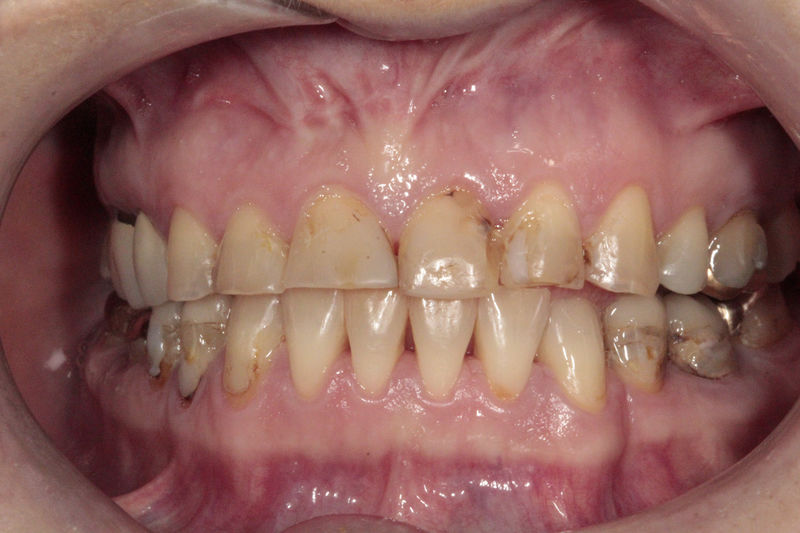

Proceso fundamental y exhaustivo que realiza el odontólogo para identificar la condición de la cavidad oral e identificar tanto zonas que esten sanas como aquellas que no lo son y buscar la causa de cualquier enfermedad o anomalía en la cavidad oral. No se limita a buscar caries, sino que ofrece una evaluación integral que sirve de base para diseñar un plan de tratamiento adecuado, efectivo y personalizado.

Disciplina fundamental de la Odontología enfocada en el diagnóstico, prevención y tratamiento restaurador de las piezas dentales que han sufrido daños. Su objetivo principal es devolver al diente su equilibrio biológico, funcional y estético cuando su integridad ha sido alterada. Resinas directas, incrustaciones, coronas.

Amplia gama de tratamientos para mejorar la apariencia de la sonrisa, corrigiendo el color, la forma, el tamaño, la alineación y la posición de los dientes. Los procedimientos más comunes y solicitados incluyen el blanqueamiento dental, las carillas y coronas, así como las resinas.